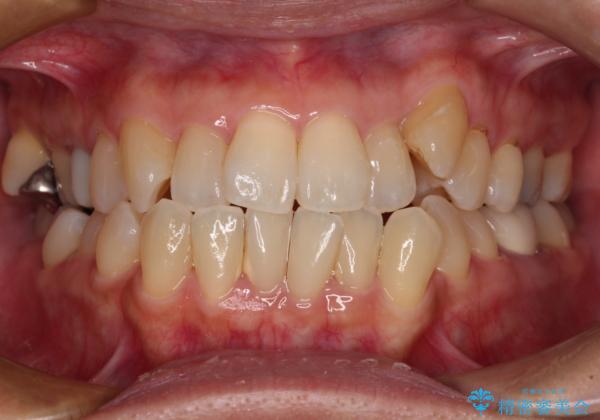

- 前歯のデコボコや八重歯を治したいとのことで来院された患者様です。

受け口傾向の骨格であり、前歯はクロスバイトまたは切端咬合となっており、下顎を中心に歯列全体の後方移動を行い、IPR(歯と歯の間を削る)によってデコボコが解消するように設計し、インビザラインにより治療を行うこととしました。

受け口傾向のインビザライン矯正は比較的治療を行いやすいため、きれいに仕上げることができました。舌の突出癖が顕著であったため、改善のためのトレーニングをしっかりと行っていただきました。